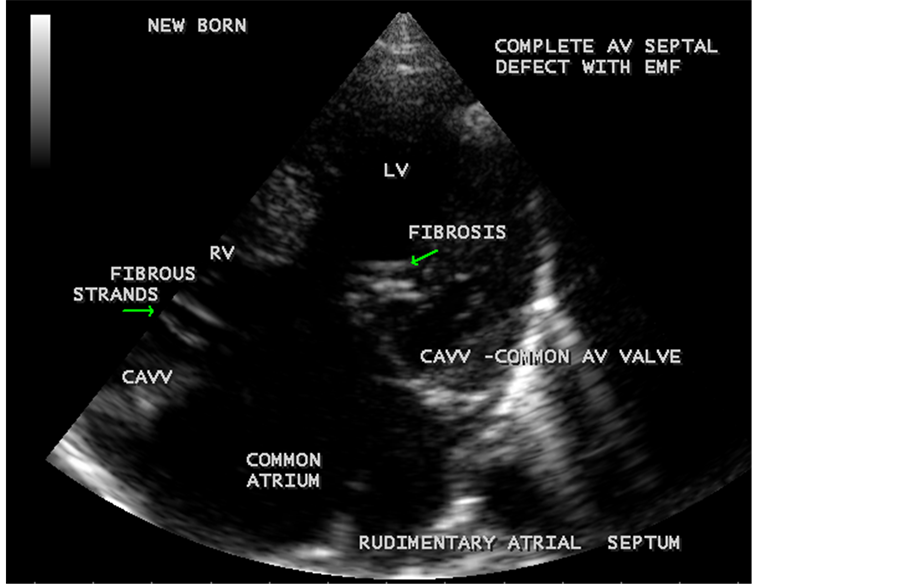

Figure 68. Showing the complete AV septal defect with fibrosis of CAVV (common AV valve) in a new born with EMF.

Figure 69. Showing the common AV (atrioventricular) valve which is thickenned and fibrosed in a newborn with EMF (endomyocardial fibrosis).

Figure 70. Showing the calcification of CAVV (common AV valve) and endocardial calcification of left ventricle in complete AV septal defect with EMF in new born.

Figure 71. Showing the subvalvular fibrosis of the CAVV (common AV valve) in EMF.

Figure 72. Showing the CAVV (common AV valve) regurgitation in new born.

RV EMF was detected antenatally in a 22-year-old woman with 8 months amenorrhea as in Figure 67. Endomyocardial fibrosis with left ventricular endocardial calcification and subvalvular fibrosis was detected in a new born with complete AV (atrioventricular) septal defect as shown in Figure 68 to Figure 72. EMF associated with fibrosis of papillary muscle and aneurysmal left ventricle is shown in Figure 74 and Figure 75 in a 56-year-old female. RV EMF associated with right sided pleural effusion, massive ascites and smoke (spontaneous echo contrast) in both ventricles are shown in Figure 76 to Figure 82 in a 42-year-old male. Classical case of RV EMF was shown in Figure 83 and Figure 84 in a 55-year-old male.